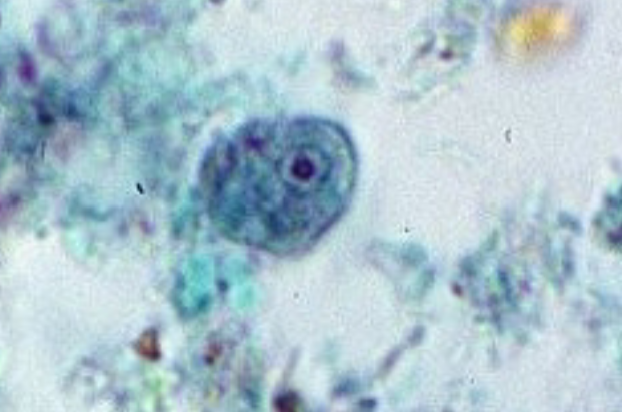

Entamoeba histolytica (cyst) >10

Entamoeba histolytica (cyst)

Entamoeba histolytica (cyst)